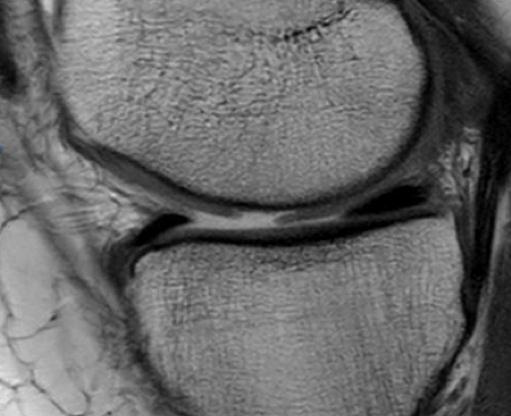

IntroducciónEl trasplante osteocondral autólogo es una alternativa quirúrgica en lesiones focales del cartílago articular. El objetivo de nuestro trabajo fue evaluar una serie de 62 pacientes tratados con mosaicoplastía de rodilla con 8 años promedio de seguimiento.Material y métodosEvaluamos retrospectivamente 62 pacientes operados con mosaicoplastía entre el año 2001 y 2014. Se incluyeron pacientes con lesión de cartílago focal de la rodilla a los que se les realizó mosaicoplastía aislada o asociada a otros procedimientos quirúrgicos (reconstrucción de LCA, osteotomía). Con un seguimiento mínimo de 2 años. Se evaluaron con las escalas de Lysholm e IKDC y el grado de artrosis con la escala radiográfica de Kellgren-Lawrence.ResultadosCuarenta y cinco fueron hombres y 17 mujeres. La edad promedio fue de 36 años. Treinta y cinco en cóndilo interno, 12 cóndilo externo, 12 tróclea y 3 combinadas. Cuarenta y dos fueron mosaicoplastías aisladas y 20 asociados a otro procedimiento. El resultado promedio de la escala de Lysholm al momento de la evaluación fue 80.1 y el IKDC fue 66.7. No encontramos diferencias significativas en la escala de Lysholm e IKDC entre los grupos de mosaicoplastía aislada y asociada a otro procedimiento. En 30 pacientes evaluados con radiografía se observó una inclusión satisfactoria del taco óseo.ConclusionesDentro de las opciones quirúrgicas se encuentran las microfracturas, el auto/alo injerto osteocondral y el implante de condrocitos autólogos. Todas estas técnicas han demostrado mejorar el estado clínico en comparación con el estado preoperatorio independientemente de cuál se utilice. En nuestra serie de pacientes operados con mosaicoplastía encontramos resultados satisfactorios en las evaluaciones clínicas.Consideramos que la mosaicoplastía es un procedimiento con alto grado de satisfacción y buenos resultados funcionales en pacientes con lesiones focales del cartílago articular. AbstractIntroduction: Osteochondral autograft transplantation is a surgical alternative for osteochondral defects of the knee. The aim of this study was to analyze a series of 62 patients treated with osteochondral autograft transplantation of the knee and an average follow-up of 8 years.Methods: A total of 62 patients treated with osteochondral autograft transplantation between 2001 and 2014 were evaluated. Patients with focal osteochondral lesions who underwent osteochondral autograft transplantation alone or associated with another procedure and a minimum follow-up of 2 years were included. Lysholm score, IKDC, and Kellgren- Lawrence radiographic scale were used. Forty-five men and 17 women (average age 36 years) were evaluated. Lesions were localized in medial condyle (35), lateral condyle (12), patella (12), and three were combined. Forty-two patients underwent isolated osteochondral autograft transplantation while 20 patients underwent associated surgical procedures.Results: Mean Lysholm score was 80.1 and IKDC score was 66.7. There were no significant differences in the Lysholm and IKDC scores between groups. Radiographic results demonstrated complete graft incorporation in 30 patients. Clinical evaluation revealed satisfactory results.Conclusion: Osteochondral autograft transplantation to treat osteochondral lesions is a procedure with a high clinical satisfaction and good functional results in patients with focal osteochondral lesions.Descargas